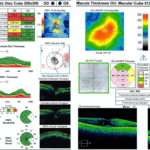

Importance of Ancillary Testing for Voriconazole-Induced Short Term Transient Visual Disturbances

by Caitlyn E. Raia, OD and Mayur Bhavsar OD, FAAO | May 10, 2024 | Medications, Volume 2, Issue 2 | 0 |

Voriconazole is in the class of triazole antifungal medications which can cause various ocular side effects including subjective visual disturbances. This emphasizes the importance of ancillary testing to evaluate for ocular toxicity